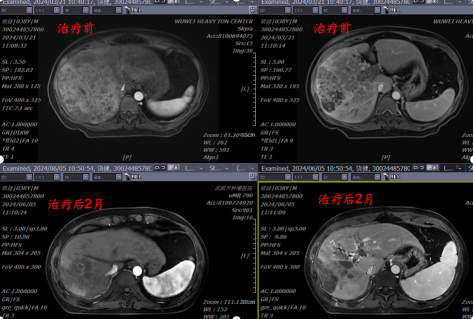

(1)、病例展示一:巨块型肝细胞肝癌合并门静脉癌栓

确诊肝癌并治疗后4月余复诊,伴有高热。腹部核磁:肝右叶异常强化灶,考虑肿瘤性病变;门静脉右支及门静脉主干管腔内见低密度影填充,考虑栓子形成。

病理诊断:肝细胞肝癌。治疗方案:碳离子放疗,总剂量:PTV:70Gy(RBE)/10Fx。同步治疗:阿替利珠单抗注射液+甲磺酸仑伐替尼胶囊。

影像学对比